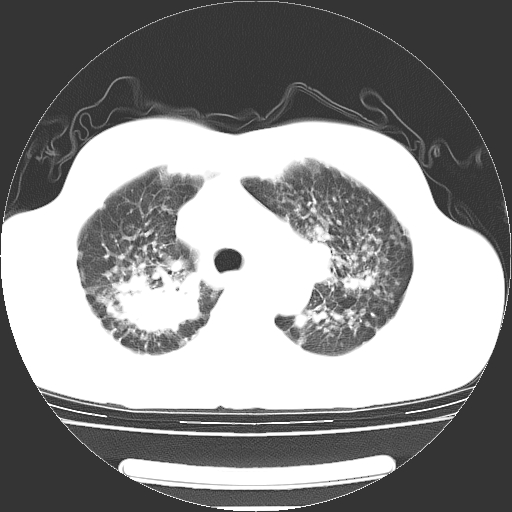

以下是引用yangyudong333在2008-4-29 5:38:00的发言:[br]比较典型的矽肺结节.支持[br]诊断依据:[br] 1.x线表现:[br] ①典型矽肺为多发直径 1~3mm 小结节,即矽结节,由胶原纤维和硅尘构成,可融合成团块,好发于上肺。[br] ②团块周围常有肺大泡。[br] ③胸内淋巴结增大、钙化。如肺门淋巴结呈蛋壳样钙化有助于与其他尘肺区别。[br] ④胸膜常广泛粘连、增厚。[br] 2.ct表现[br] ①两肺散在大小较为一致的小结节影,其密度较高,边界清楚。[br] ②小结节可融合为较大团块影,直径约 1cm ,甚至可达 10cm以上,易发生在上叶。[br] ③小结节周围常并有小叶中心气肿或弥漫性肺气肿。

以下是引用liuyue在2008-4-28 22:30:00的发言:[br]比较典型的矽肺结节.[br]请结合临床及化验除外矽肺合并肺结核之可能.